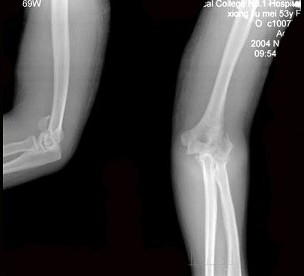

53岁女性患者,因摔倒时手掌着地,感右肘关节肿痛、畸形,X线摄片如图所示,下列正确的诊断是()

A:右肱骨外髁骨折

B:右肱骨内上髁骨折

C:右肱骨外上髁骨折

D:右肱骨小头骨骺分离

E:右肱骨内髁骨折